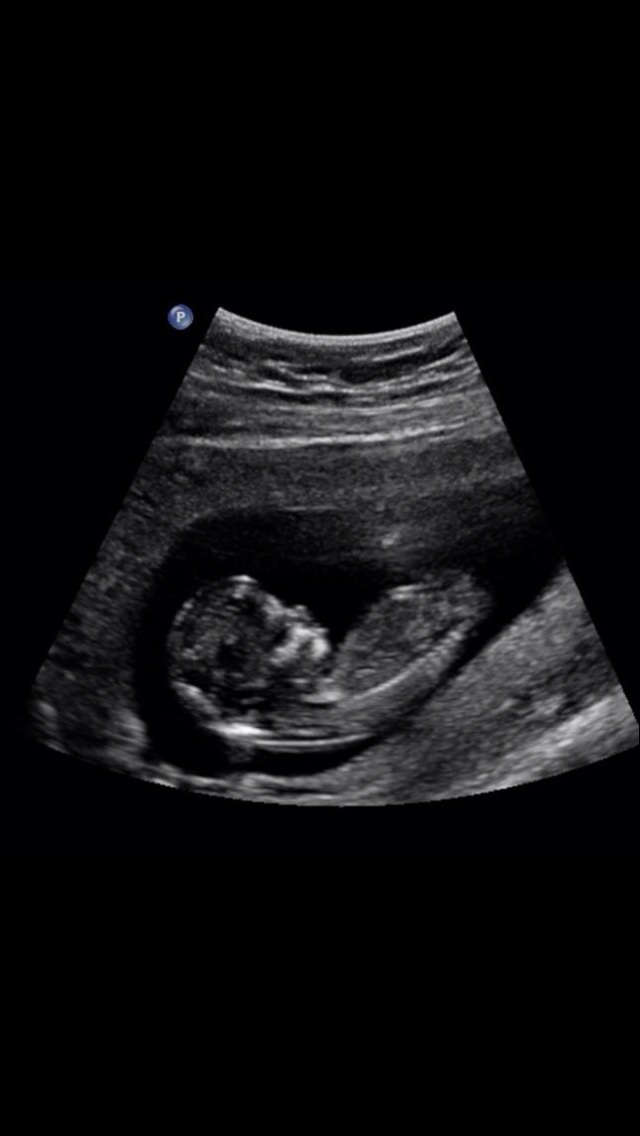

Here is another photo can anyone tell me if that is a nub on the end??Attachment 20313